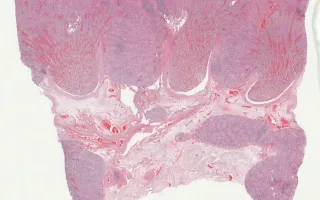

Kidney, Cytomegalovirus, H&E stain

Diagnosis

Autopsy of stillborn fetus; fetal kidney section shown.

Cytomegalovirus is the most common neonatal viral infection. It is a member of the Herpesviridae, double-stranded DNA virus group (HHV-5). Characteristic histologic features include the classic "owl's eye" inclusions, which are readily visible at low power. In the kidney, the affected cells include tubular epithelium, glomerular epithelium, and peritubular capillary endothelial cells. Renal involvement is usually associated with systemic involvement. In this case, the virus resulted in intrauterine death. Uncompromised immunity generally results in benign, self-limiting disease. Long-term sequelae of congenital infections can include hearing impairment, motor deficits, and cognitive impairment.

This slide shows H&E stain. See related content for IHC slide.